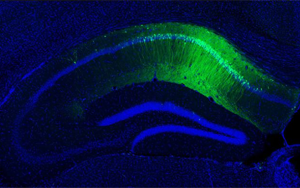

德國維爾茨堡大學醫院(University Hospital Wuerzburg)的Abdolhossein Zare和Saeede Salehi等研究人員開展了一項突破性研究。他們發現RNA結合蛋白hnRNP R能特異性結合tau編碼基因Mapt mRNA的3'非翻譯區(3'UTR),促進其在軸突中的定位和局部翻譯。通過構建hnRNP R基因敲除小鼠與5xFAD AD模型小鼠雜交,研究人員觀察到這些小鼠大腦中磷酸化tau聚集和Aβ斑塊顯著減少。